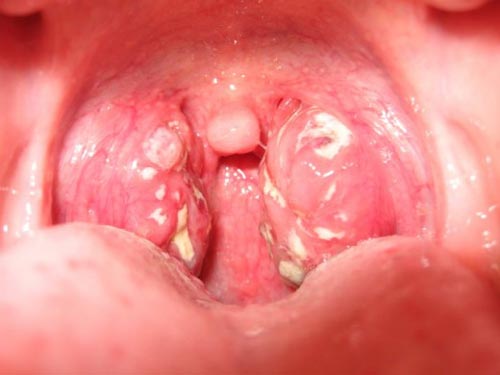

Nhiều người cho rằng bình ảnh bệnh lậu trong miệng không hình thành nhưng điều này hoàn toàn có thể diễn ra. Khi quan hệ với người bị nhiễm qua đường miệng thì nguy cơ lây nhiễm cực kỳ cao. Một số hình ảnh về căn bệnh lậu ở miệng:

- Tại cổ họng sưng và đỏ

- Cổ họng loét và ho,

- Có hiện tượng sưng amidan